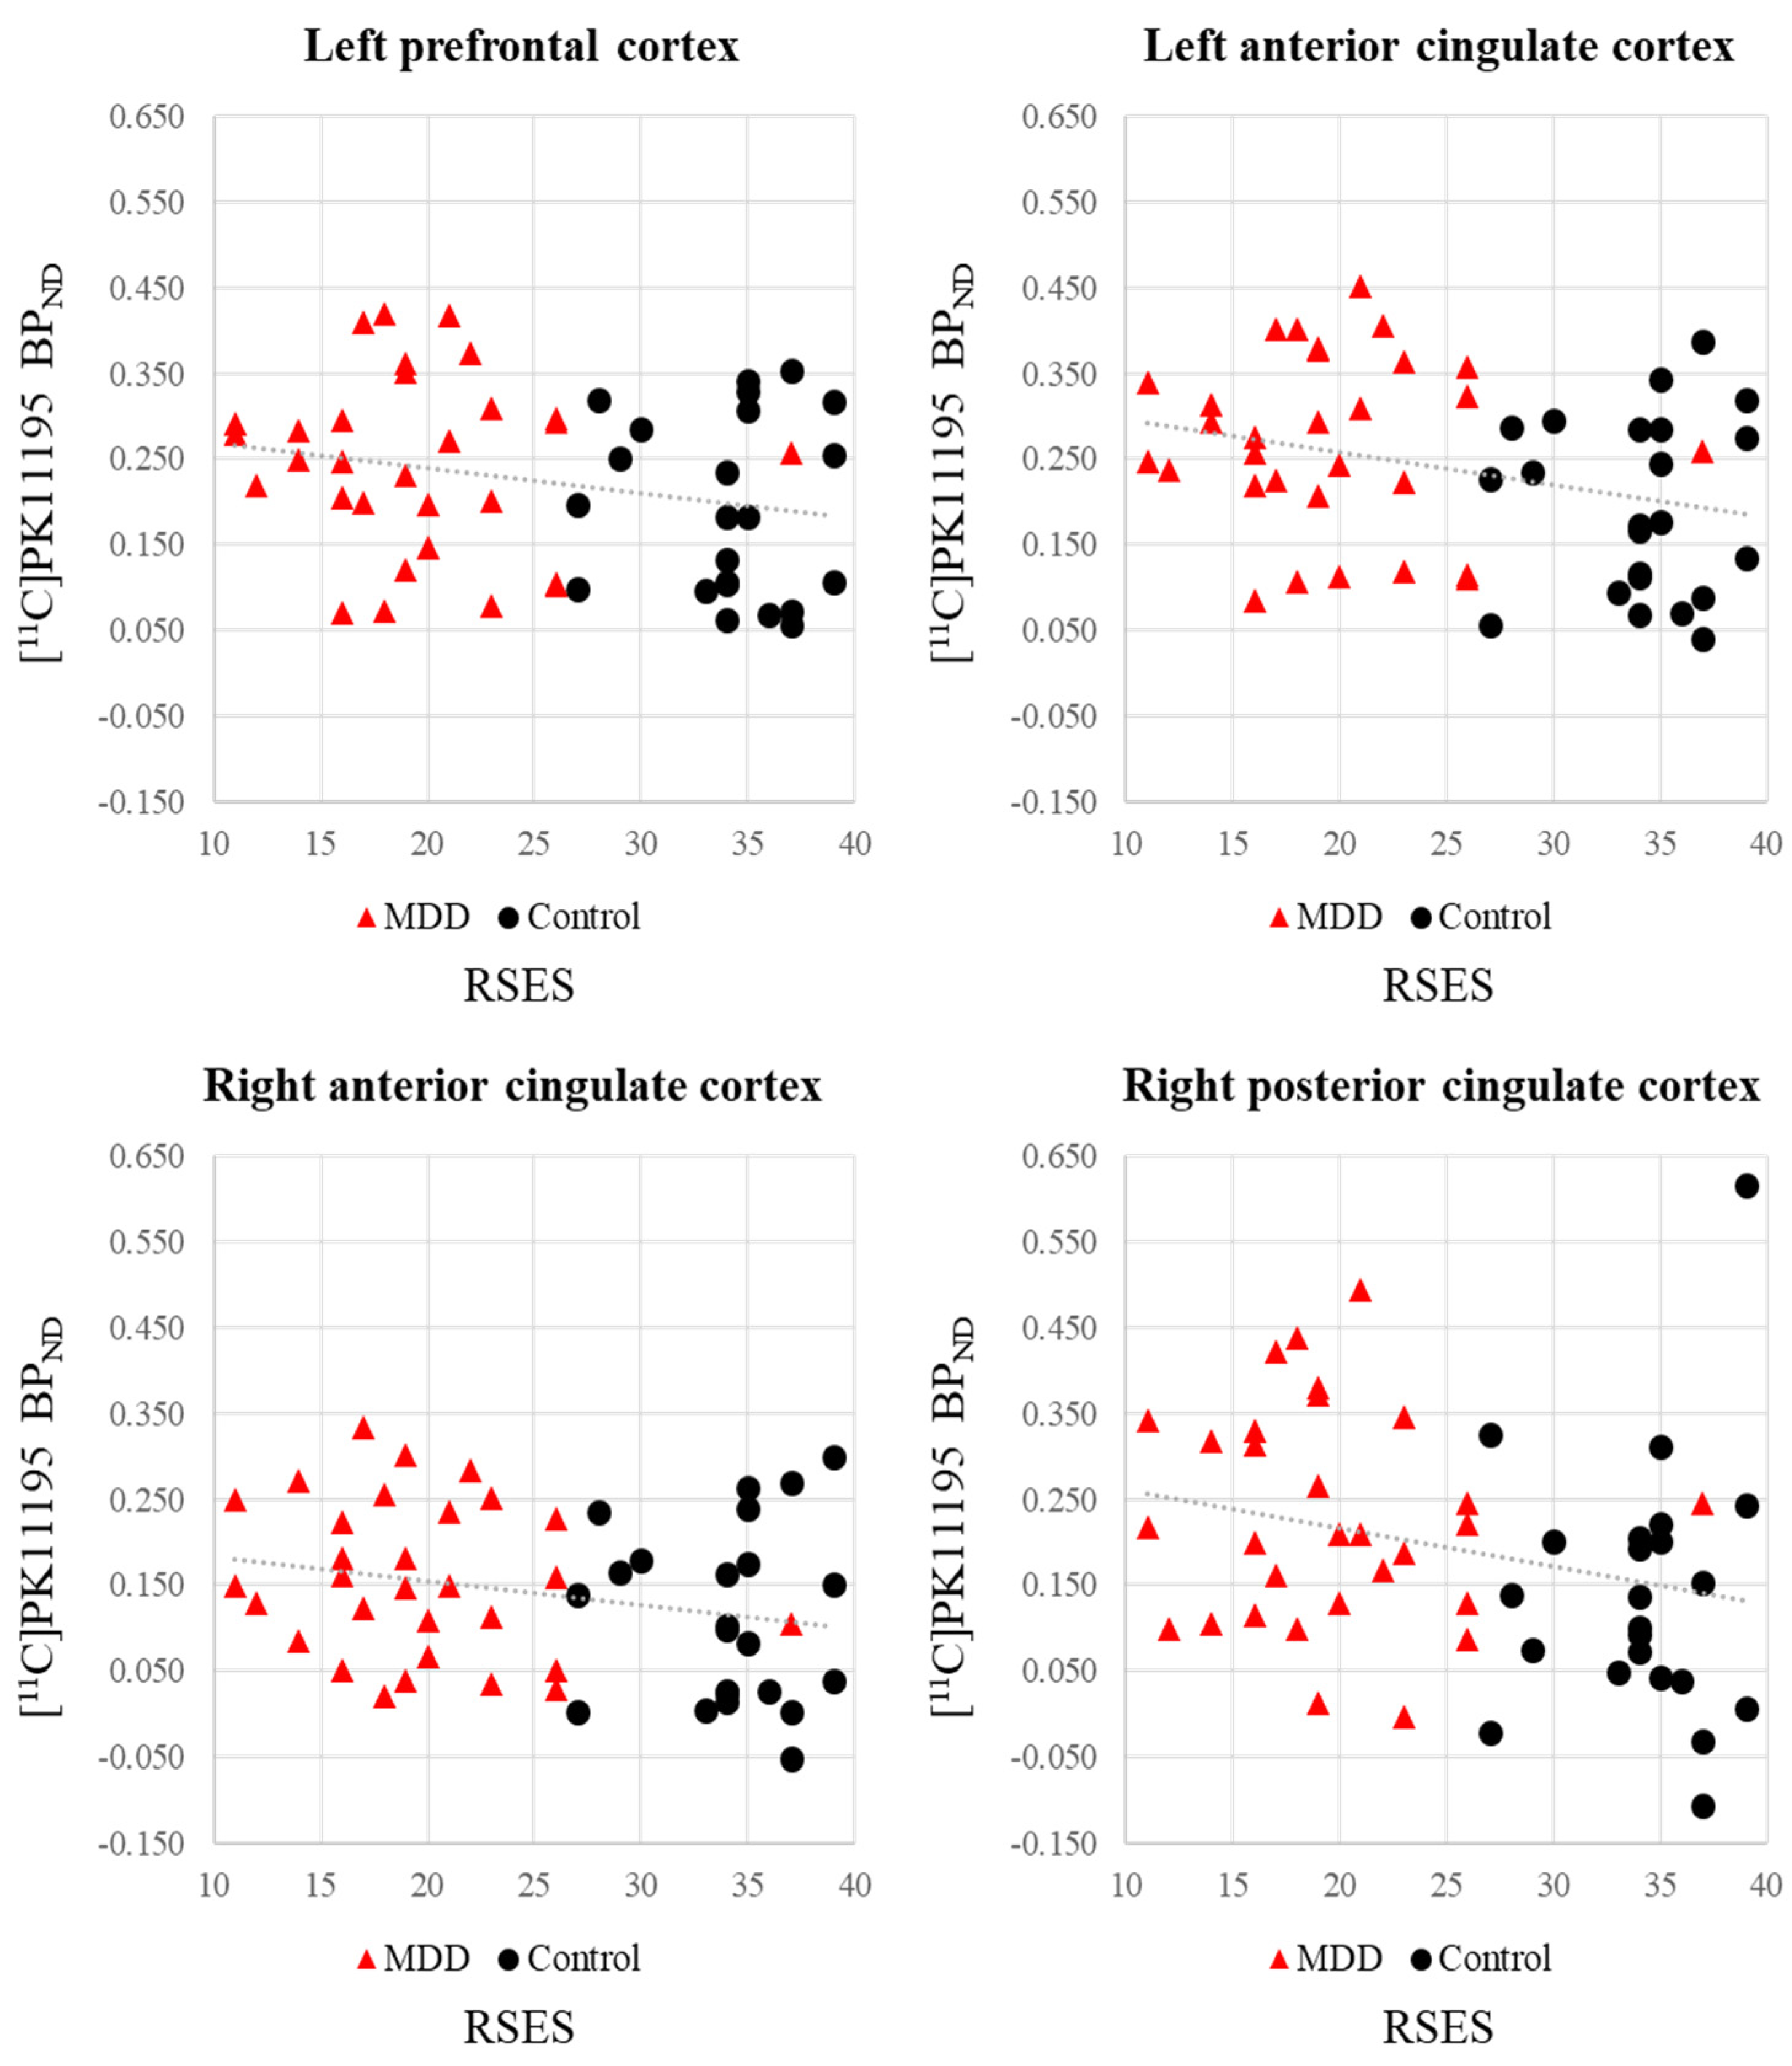

| ROIs | RSES | BIS | ||

|---|---|---|---|---|

| r-Value | p-Value | r-Value | p-Value | |

| Lt. prefrontal cortex | −0.242 | 0.081 † | 0.114 | 0.416 |

| Rt. prefrontal cortex | −0.220 | 0.114 | 0.098 | 0.484 |

| Lt. anterior cingulate cortex | −0.301 | 0.029 * | 0.165 | 0.238 |

| Rt. anterior cingulate cortex | −0.248 | 0.074 † | 0.159 | 0.255 |

| Lt. posterior cingulate cortex | −0.203 | 0.144 | 0.163 | 0.244 |

| Rt. posterior cingulate cortex | −0.269 | 0.052 † | 0.198 | 0.155 |

| Lt. insula | −0.220 | 0.113 | 0.144 | 0.303 |

| Rt. Insula | −0.206 | 0.139 | 0.105 | 0.455 |

| Lt. hippocampus | −0.149 | 0.285 | 0.099 | 0.479 |

| Rt. hippocampus | −0.126 | 0.370 | 0.175 | 0.211 |

| Lt. temporal cortex | −0.217 | 0.119 | 0.111 | 0.429 |

| Rt. temporal cortex | −0.212 | 0.127 | 0.106 | 0.448 |